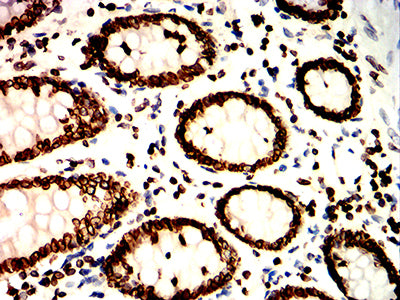

Immunohistochemical analysis of paraffin-embedded human colon tissues using LMNB1 mouse mAb with DAB staining.